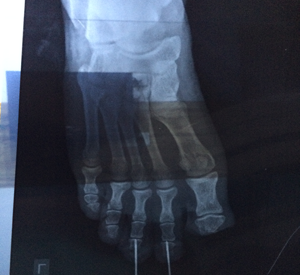

Trauma Surgery

Trauma Surgery is a surgical speciality that utilizes both operative and non-operative management to treat traumatic injuries, typically in an acute setting.